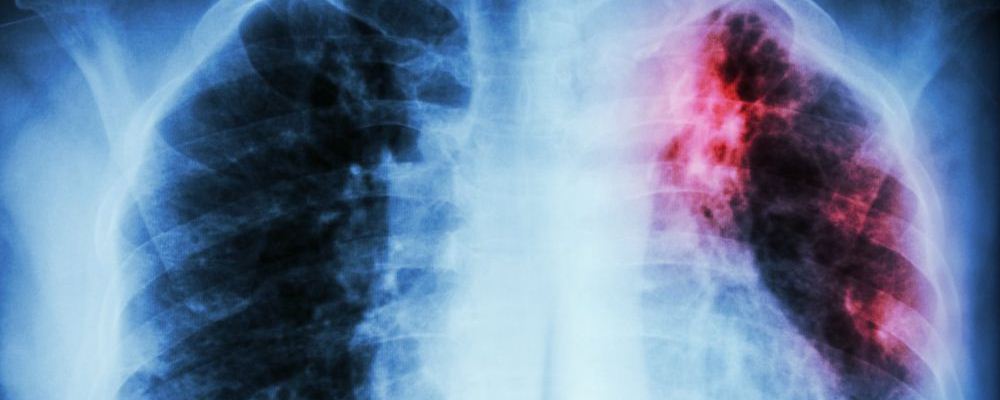

肺癌可是很可怕的疾病,其發(fā)病率和死亡率都很高,是一種威脅人的健康和生命的惡性腫瘤。早期發(fā)現(xiàn)問(wèn)題治療恢復(fù)的可能性比較大,可是到了肺癌晚期的時(shí)候,就算就回來(lái)了也沒幾年好活了??墒牵罱嫌袀€(gè)家庭發(fā)生了一件糟心的事情——12男孩患上原發(fā)性支氣管肺癌晚期疾病。這實(shí)在是令人震驚,這么小的年紀(jì)就得了這種病。

近日,湖南邵陽(yáng)一名12歲男孩因鎖骨處長(zhǎng)包塊,到醫(yī)院檢查,竟然得了原發(fā)性支氣管肺癌晚期!這種癌癥患病率和死亡率位居全球第一,但在未成年人中比較罕見。而造成此種疾病的原因,竟然是“懶,經(jīng)常熬夜,早餐基本上不吃!”